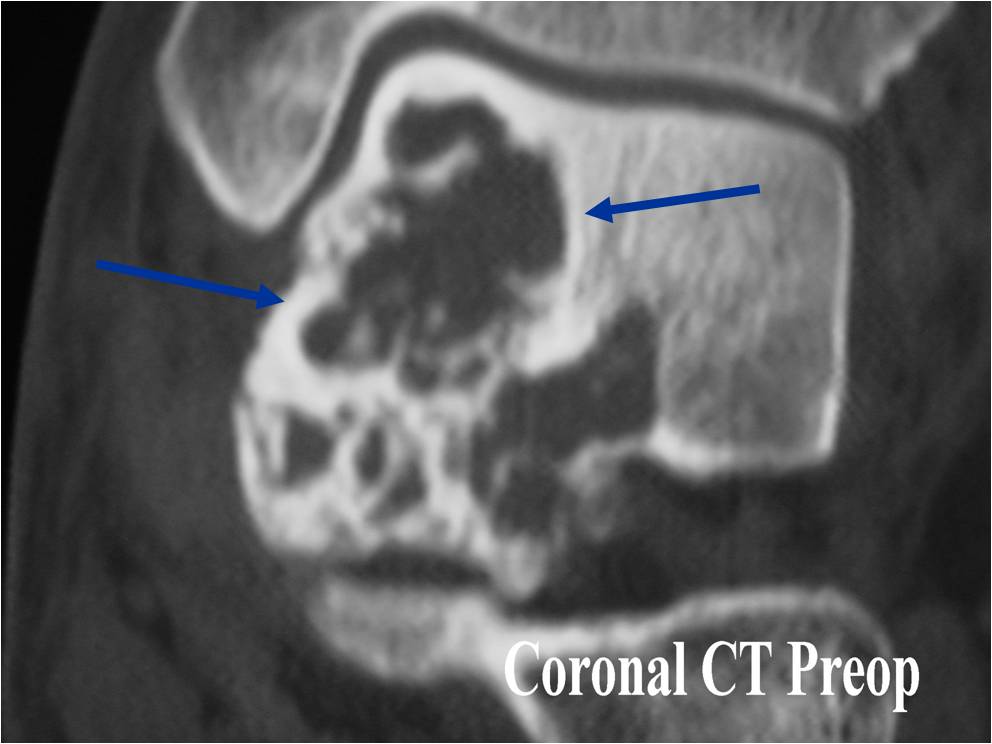

General Information Enchondroma is a benign indolent intramedullary hyaline cartilage neoplasm Accounts for 10% of all benign osseous tumors Limited growth, most lesions are less than 5 cm in maximal dimension Bones grow from a cartilaginous growth plate that...